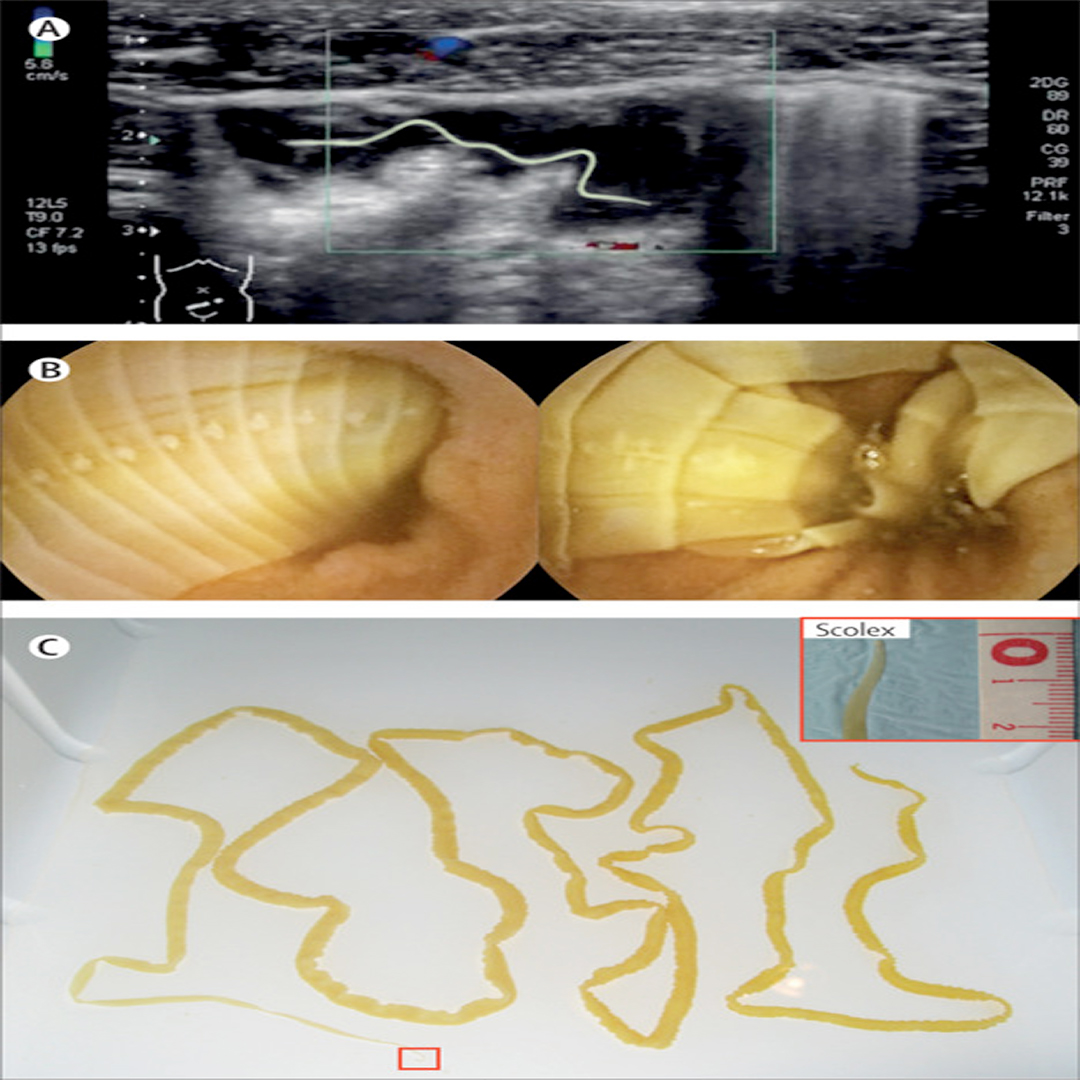

Answer: 210cm Intestinal diphyllobothriasis thelancet.com/journals/lance…

UTHSCPAprogram's tweet image. Answer:  210cm Intestinal diphyllobothriasis

thelancet.com/journals/lance…